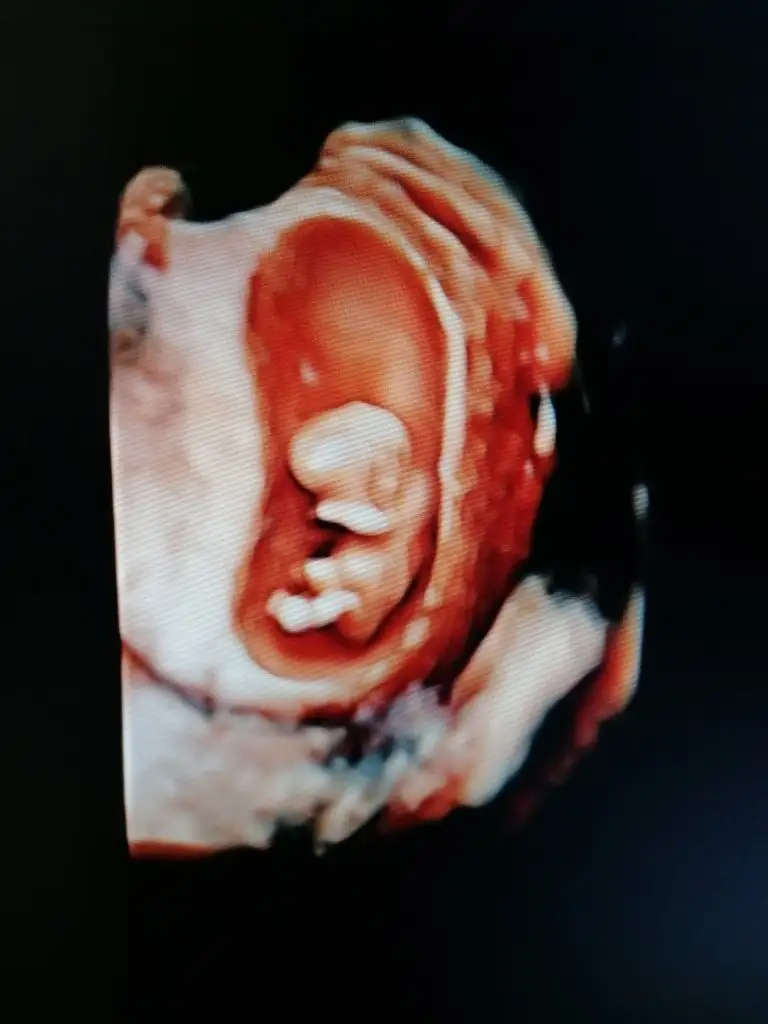

Merhaba, benim bebişi de bakabilir misiniz..

• IMG_20240315_092551.webp

IMG_20240315_092551.webp

21,2 KB · Görüntüleme: 66

10+1 karından çekildi